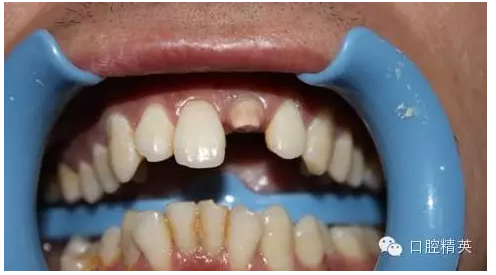

一年輕小伙,在打籃球中,被隊友打斷門牙,來本診所時已經(jīng)露髓,局麻拔髓后,行RCT。后因經(jīng)濟(jì)關(guān)系,擬鈷鉻樁加鈷鉻烤瓷冠修復(fù),備牙后才留照片:

1:牙根,備牙后,

2:唇側(cè)觀,

術(shù)前 ↑

術(shù)后 ↓

11:正面微笑圖